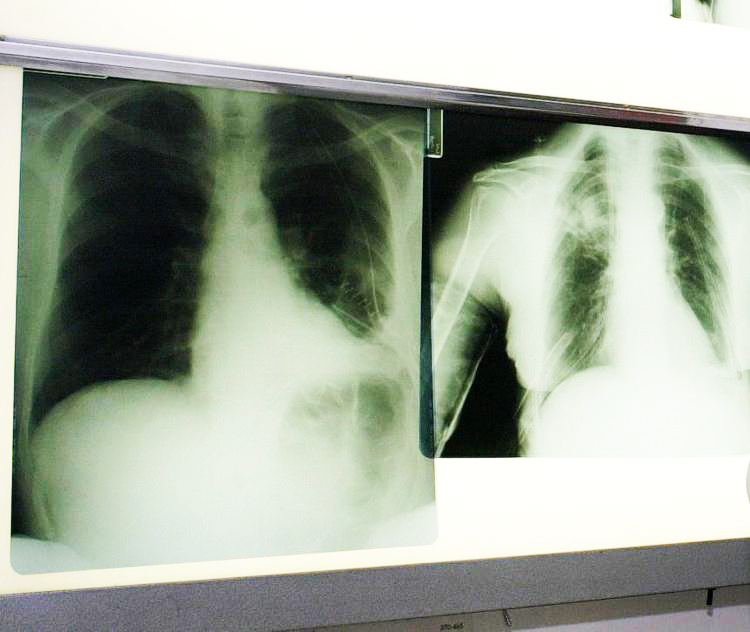

Takeda Italia annuncia la disponibilità anche per i pazienti italiani di brigatinib (Alunbrig*) in monoterapia per il trattamento di pazienti adulti con cancro del polmone non a piccole cellule (Nsclc), avanzato, Alk positivo (chinasi del linfoma anaplastico), non trattati precedentemente con inibitori Alk, che affianca l’indicazione al trattamento in monoterapia di pazienti adulti con Nsclc positivo per Alk, in stadio avanzato, precedentemente trattati con crizotinib, ottenuta il 26 ottobre 2020. Brigatinib è un inibitore della tirosin-chinasi di nuova generazione studiato per colpire selettivamente e inibire le alterazioni genetiche Alk.

Lo studio registrativo di fase 3 Alta-1L, che ha valutato la sicurezza e l’efficacia di brigatinib in confronto a crizotinib nei pazienti con Nsclc Alk positivo, localmente avanzato o metastatico, che non hanno ricevuto precedente trattamento con un inibitore Alk, ha evidenziato una significativa efficacia sistemica di brigatinib, che ha ridotto del 51% il rischio di progressione della malattia o decesso rispetto a crizotinib.

I risultati dello studio – spiega una nota – evidenziano l’efficacia di brigatinib nella popolazione Itt, “intent to treat”, con una sopravvivenza libera da progressione mediana doppia in confronto a crizotinib: 24 mesi rispetto a 11, come valutato dal comitato di revisione indipendente in cieco. “Nel trattamento del carcinoma polmonare non a piccole cellule assume sempre maggiore rilevanza la profilazione molecolare del tumore, che permette di ampliare le opportunità terapeutiche a disposizione per specifiche tipologie di pazienti”, commenta Paolo Marchetti, professore ordinario di oncologia alla Sapienza, Università di Roma. “Nel caso dei pazienti con tumore del polmone non a piccole cellule avanzato, che presenta riarrangiamento del gene Alk, brigatinib, rappresenta una importante alternativa a disposizione, avendo dimostrato nello studio clinico registrativo un’efficacia sistemica significativamente maggiore rispetto al farmaco di confronto”.